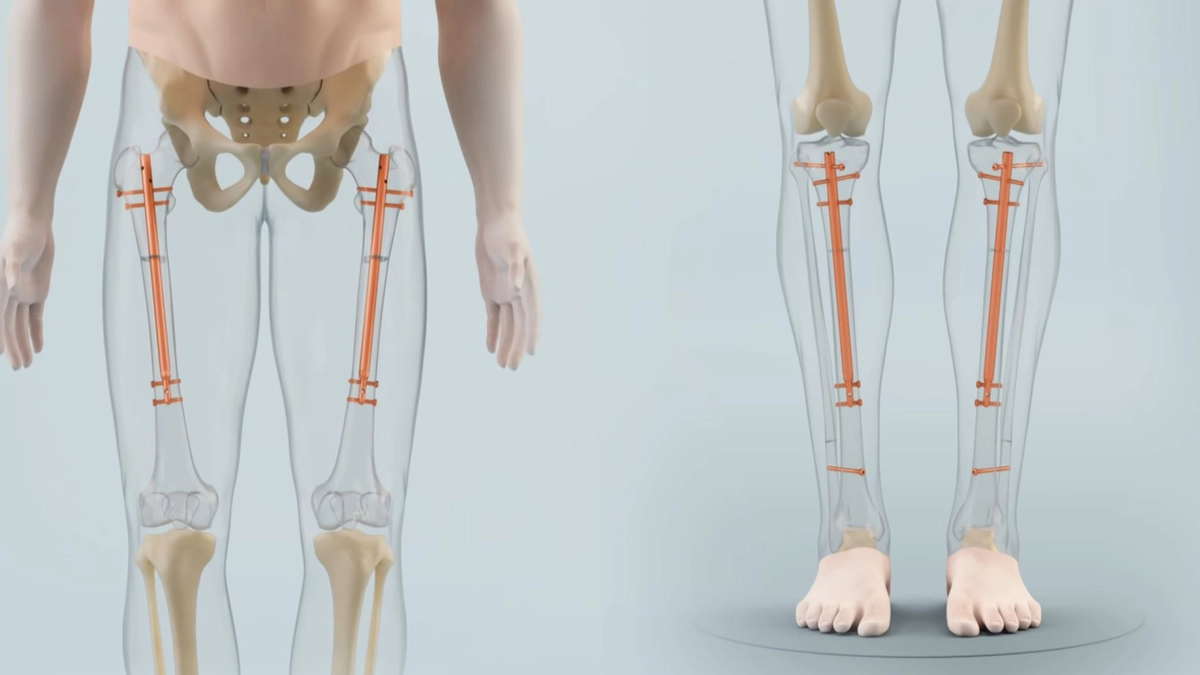

İnsan kemikleri, çocukluk ve ergenlik döneminde büyüme plakaları (epifiz plakları) adı verilen özel kıkırdak bölgeler aracılığıyla uzar. Bu plakalar, uzun kemiklerin uç kısımlarında bulunur. Zamanla bu plakalar kemikleşerek kapanır ve uzama sona erer.

Kızlarda büyüme plakaları genellikle 16-17 yaşlarında kapanır.

Erkeklerde ise bu süreç 18-21 yaşlarına kadar sürebilir.

Büyüme plakaları kapandıktan sonra doğal yollardan boy uzaması durur.